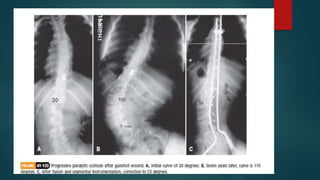

XRAY VIEWS  Erectfilms include anteroposterior and lateral views of the spine from the occiput to the sacrum  Spot lateral and oblique views of the lumbosacral junction are taken to study this area for spondylolisthesis or spondylosis  Lateral bending films are taken to 1)determine the degree of flexibility of spine 2)to see how much each curve can be passively corrected 3)to distinguish structural curves from non structural

• 30.

MEASUREMENT OF CURVES Measurement of curves is based on determining the upper and lower end vertebra  The superior end vertebra is the last one at the upper end of the curve that tilts towards the concavity  The inferior end vertebra is the last one at the lower end that tilts towards the concavity  The apical vertebra is the one deviated farthest from the vertebral column